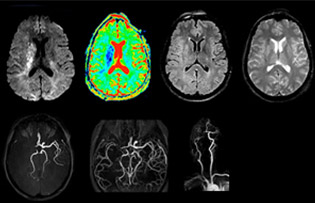

Foundation Rothschild, a hospital specialized in head and neck care, exploits Ingenia 3.0T for imaging multiple sclerosis, stroke, and brain tumors.

In any type of neurological MRI, it’s crucial to gather as much information as possible to increase diagnostic confidence. Whether it’s an exam for MS, brain tumor, or stroke, scanning must be fast and efficient, and images must provide high detail. Ingenia 3.0T is ideal for demanding brain imaging due to its high SNR, good spatial resolution, and flexibility to accommodate many different protocols.

Comprehensive exam answers complex brain tumor questions

Dr. Savatovsky uses five or six different ExamCards for imaging a mass or a known tumor in the brain. “If there is a mass in the brain we try to characterize it to inform the neurologist for determining next steps or to help neurosurgeon prepare for a surgery or biopsy. For follow-up after treatment we have different protocols for different treatments and we adapt for intra- or extra-axial tumors.”

“The biggest challenges are properly characterizing the lesion and giving the surgeon all the information needed, such as the location of vessels and functional areas. Sometimes a very comprehensive exam is necessary, such as when a mass has been discovered at another hospital after which the patient is referred to us. We then do both lesion characterization and preoperative imaging in one exam, so both morphologic and functional assessment. For morphologic assessment we will use pre- and post-contrast T1-weighted imaging, FLAIR to assess infiltration, and diffusion. For functional characterization we will perform perfusion, spectroscopy, and susceptibility weighted imaging to look for micro vessels or micro hemorrhage inside the lesion[4]. For preoperative imaging we perform specific morphologic imaging that is compatible with the navigation system; depending on the location of the tumor, we would do fMRI or DTI.”

“That is the most comprehensive exam we would do. Ingenia has the good spatial resolution and high SNR to provide all this information, and the flexibility to use shorter sequences, so we can do a very comprehensive examination in a limited time.”